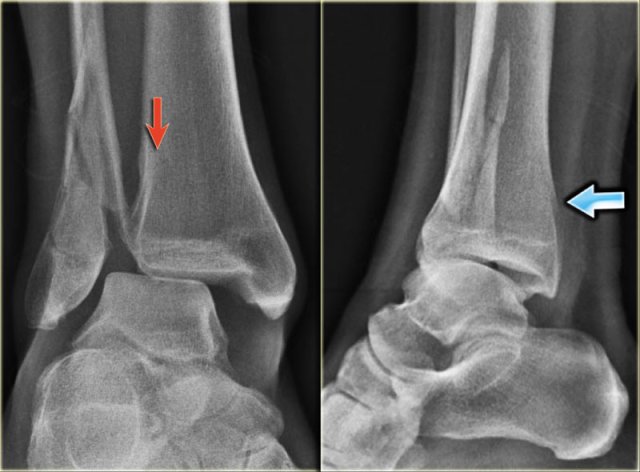

PE stage 1 PE stage 1

• Re-examination

On the ankle films there was no sign of an oblique fracture of the lateral malleolus, so we can exclude a Weber B fracture.

There is still the possibility of a Weber C fracture stage 4, i.e. medial rupture or avulsion, high fibular fracture and finally a posterior malleolus fracture.

At reexamination you notice the subtle avulsion of the medial malleolus (red arrow), which is stage 1.

Notice also the soft tissue swelling on the medial side (blue arrow)

PE stage 3 PE stage 3

Additional radiographs of the lower extremity were ordered and they demonstrate a high fibular fracture, i.e. Weber C stage 3 also known as a Maisonneuve fracture.

• Final report

Weber C fracture stage 4.

This is un unstable ankle injury that needs surgical repair.

Understanding the fracture mechanism and the stages according to Lauge-Hansen helps you to make the right diagnosis